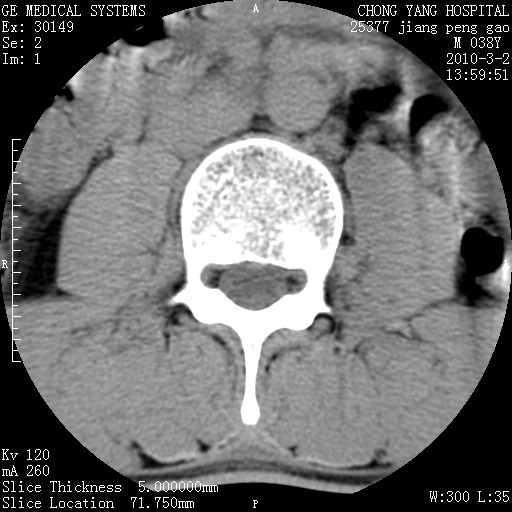

标题: CT24887:M38Y 反复腰痛 无外伤史 未做针灸 竖脊肌为何积气 [打印本页]

标题: CT24887:M38Y 反复腰痛 无外伤史 未做针灸 竖脊肌为何积气

退变,轻度增生/间盘膨出、l5椎后缘软骨结节。

肌间隙积气过多也为退变表现。